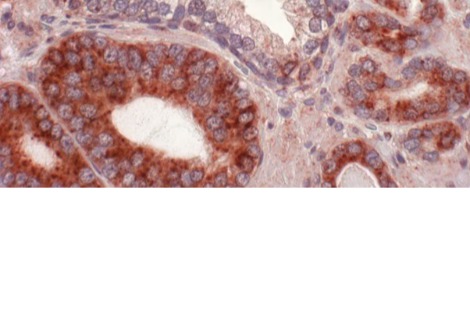

يقوم العلماء في أماكن أخرى ببذل قصارى جهدهم للوصول إلى علاج ممكن من خلال إعادة تنشيط الخلايا المناعية (تي) عن طريق هندستها وراثيّاً كي تتمكّن من مواجهة الخلايا السرطانيّة بقوّة أكبر. تسمّى هذه العمليّة بكار-تي " chimeric antigen receptor–T" حيث يتمّ تعديل المستقبِل جينيّاً ليتعامل مع الخلايا السرطانيّة بشكل أفضل باستخدام مستضدّ مستقبل تي العلاجي، ويطمح العلماء للحصول على الموافقة لاستخدام هذا العقار العام المقبل.